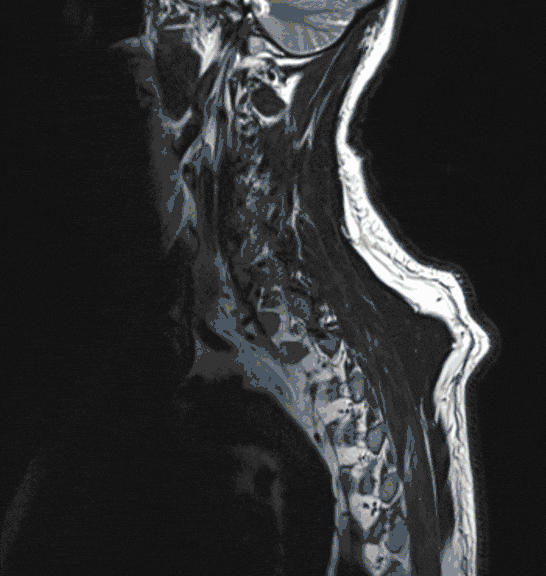

Meningeom

Meningeome sind nicht seltene Tumore, die das Rückenmark von außen bedrohen. Aufgrund ihres meist langsamen Wachstums können sie zu einer erheblichen Größe heranwachsen und dadurch die Funktion des Rückenmarks bedrohen. Sie werden deshalb meist spät erkannt, häufig erst nach Auftreten von starken Schmerzen oder Gangstörungen.

Die Therapie der Wahl ist die operative Entfernung. Gerne beraten wir Sie über diese Erkrankung und die Behandlungsmodalitäten.